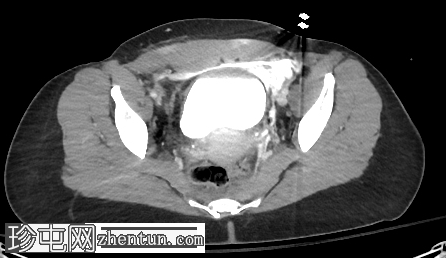

轴位增强扫描(门静脉期)

膀胱腹侧黏膜全层缺损,造影剂显影的尿液活动性外渗至盆腔。造影剂似乎局限于腹侧筋膜间隙。一条线状造影剂显影的尿液穿过下腹壁,位于腹直肌鞘内。

这是一例腹膜外膀胱破裂。